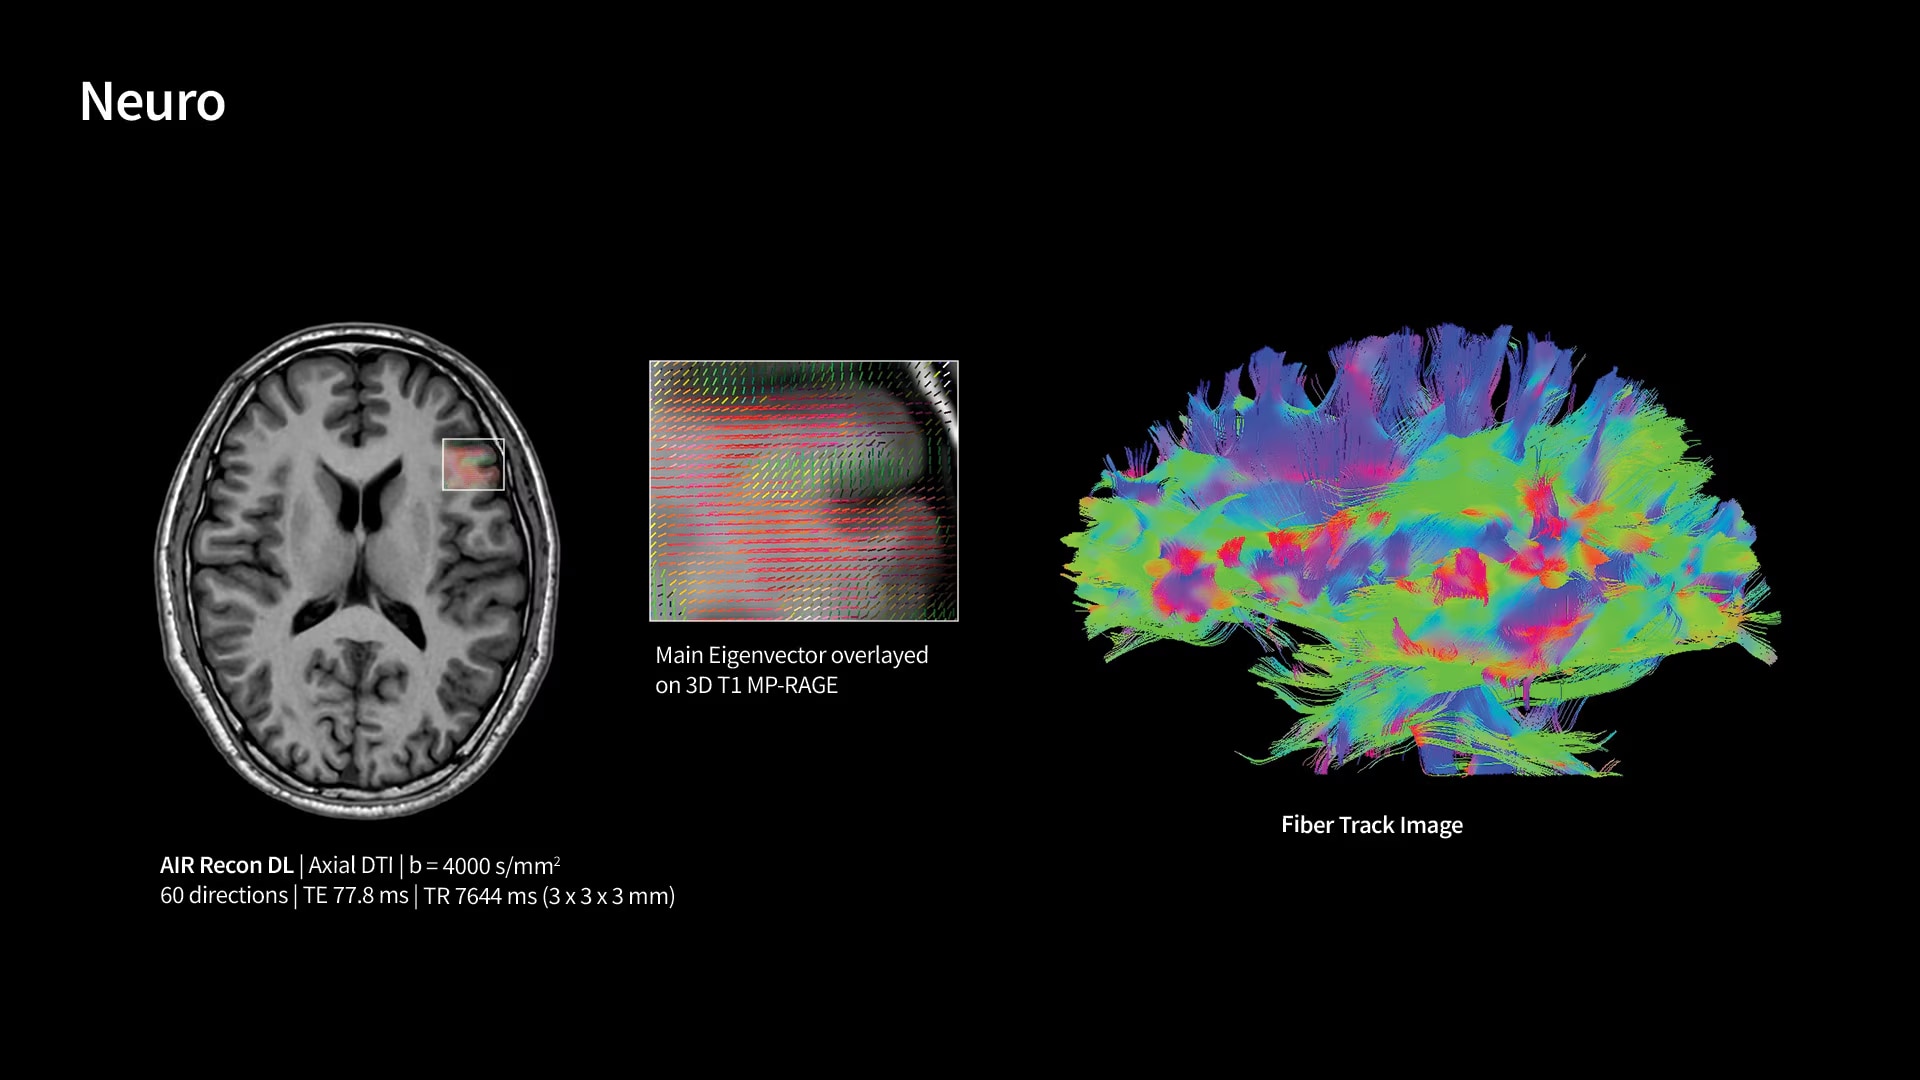

Within cardiovascular diseases, the functional assessment of the heart is an essential imaging application. SIGNA Sprint is powered by built-in AI technologies—Sonic DL™, AIR Recon DL and AIR x™—enabling high-quality imaging even in the most demanding anatomies.

With GE HealthCare's comprehensive suite of deep-learning solutions integrated into SIGNA Sprint, you can unlock the full potential of your MRI system. No need for complicated patient setups or imaging protocols. The exceptional intelligence of our AI solutions offer multiple benefits, with AIR Recon DL giving pin-sharp images, Sonic DL accelerating scans up to 12x, and AIR x enabling automated slice placement. All helping to enhance your department’s workflow efficiency, increase patient throughput, and get the diagnostic clarity you need, faster.¹ Meaning you can spend more time on what truly matters—personalized patient care, enabling optimized treatment plans and treatment response monitoring—ultimately, supporting better clinical outcomes.